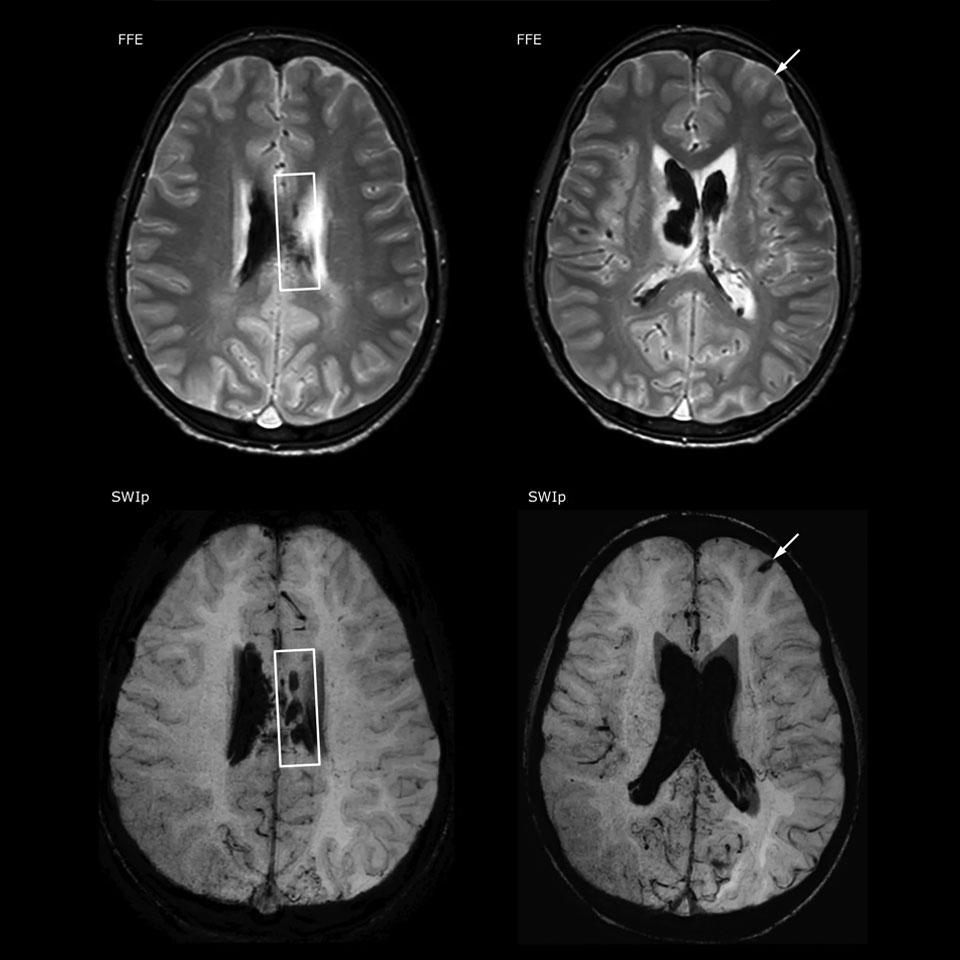

The value of susceptibility weighted imaging in visualizing brain injury is well documented. The Philips multi-echo SWIp technique provides fast susceptibility weighted imaging with enhanced susceptibility contrast and high resolution.

“SWIp helps us identify blood or blood products, calcification, and diseases that affect the vascular system,” says Dr. Miller. “In children with traumatic brain injuries, it highlights areas that are injured, better than some of the previous techniques that we were using. These children often have micro-injuries that cause small amounts of blood or tissue damage. Adding SWIp helps us to better characterize the extent and nature of the injury. Having characterized an injury to the extent of what’s possible supports our diagnostic confidence.”

Full adoption after initial comparison

“I would definitely recommend other users to implement SWIp. We initially added the SWIp sequence following a lot of support for its utility in the literature. Then we directly compared SWIp to the 2D gradient echo sequences that we were using. After a good amount of clinical experience in seeing its benefits, we were confident to replace the old sequences with SWIp. It gives us a better assessment of the physiological processes of the brain that were less apparent on our previous imaging sequences,” says Dr. Miller. “SWIp is now a routine sequence for imaging traumatic brain injury patients at PCH, and it’s episodically added for patients who have intracranial vascular abnormalities.”